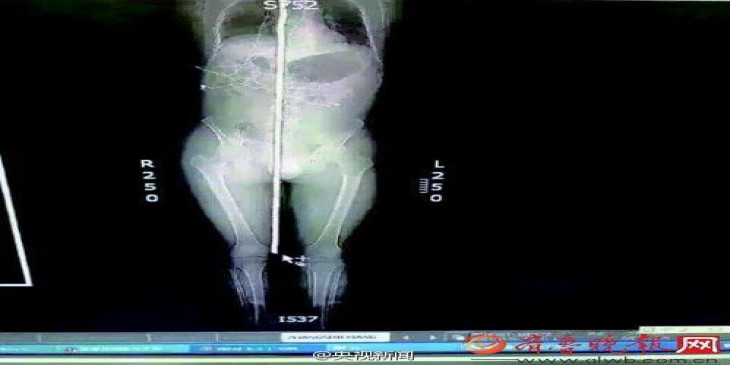

၅ ေပရွည္တဲ့ စတီးေခ်ာင္း ဦးေခါင္းကေန ခႏၶာကိုယ္ ေအာက္ပိုင္းအထိ စိုက္၀င္ခဲ့ေပမယ့္ ခြဲစိတ္ကုသခံယူခဲ့တဲ့ အတြက္ အမ်ိဳးသား တဦးဟာ အသက္ခ်မ္းသာခဲ့ပါတယ္။

ဇြန္ ၁၄ ရက္က တ႐ုတ္ႏုိင္ငံ ရွန္ေဒါင္း ခ႐ိုင္ ဂ်န္နန္ၿမိဳ႕မွာ ေဇာင္လို႔ေခၚတဲ့ လူတဦးက ေဆာက္လုပ္ေရး လုပ္ငန္းခြင္မွာ စတီးေခ်ာင္းေတြေပၚ ျပဳတ္က်ခဲ့တာ ျဖစ္ပါတယ္။

ဒီေနာက္သူ႔ကို ေဆး႐ုံတင္ပို႔ခဲ့ၿပီး ၅ နာရီၾကာ ခြဲစိတ္ကုသမႈ ခံယူခဲ့ပါတယ္။ ဆရာ၀န္ ၇ ဦးက လုံးပတ္ ၀.၇ စင္တီမီတာရွိတဲ့ စတီးေခ်ာင္းကို ျပန္ၿပီး ထုတ္ယူခဲ့ပါတယ္။

ဒီေလာက္လုံးပတ္ရွိတဲ့ စတီးေခ်ာင္းေၾကာင့္ ေသြးအမ်ားအျပားဆုံးရႈံးႏုိင္ၿပီး အသက္ေသႏုိင္သလို ေတြ႔ဖူးသမွ်ထဲမွာ အဆိုး၀ါးဆုံးတခုျဖစ္တယ္လို႔ ခြဲစိတ္မႈ ေခါင္းေဆာင္က ေျပာပါတယ္။